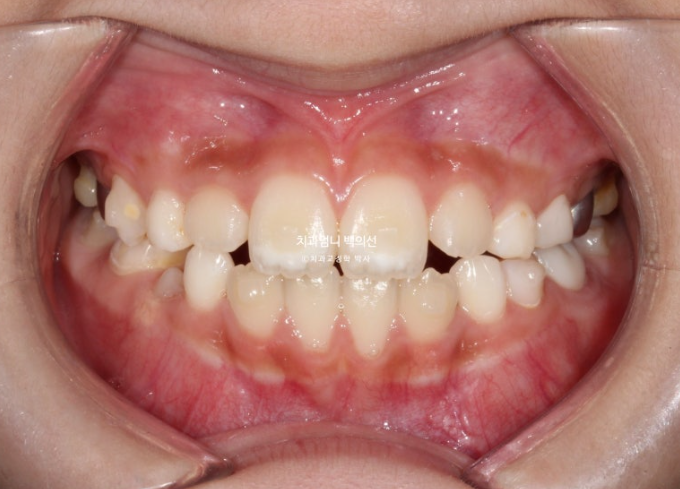

앞니 중심선은 정확히 맞고 배열은 좋습니다.

윗니가 아랫니를 정상적으로 덮지 못하는 절단교합 이었으나, 3급 고무줄로 적절한 앞니교합을 형성했습니다.

앞니 중심선의 개선이 보입니다.